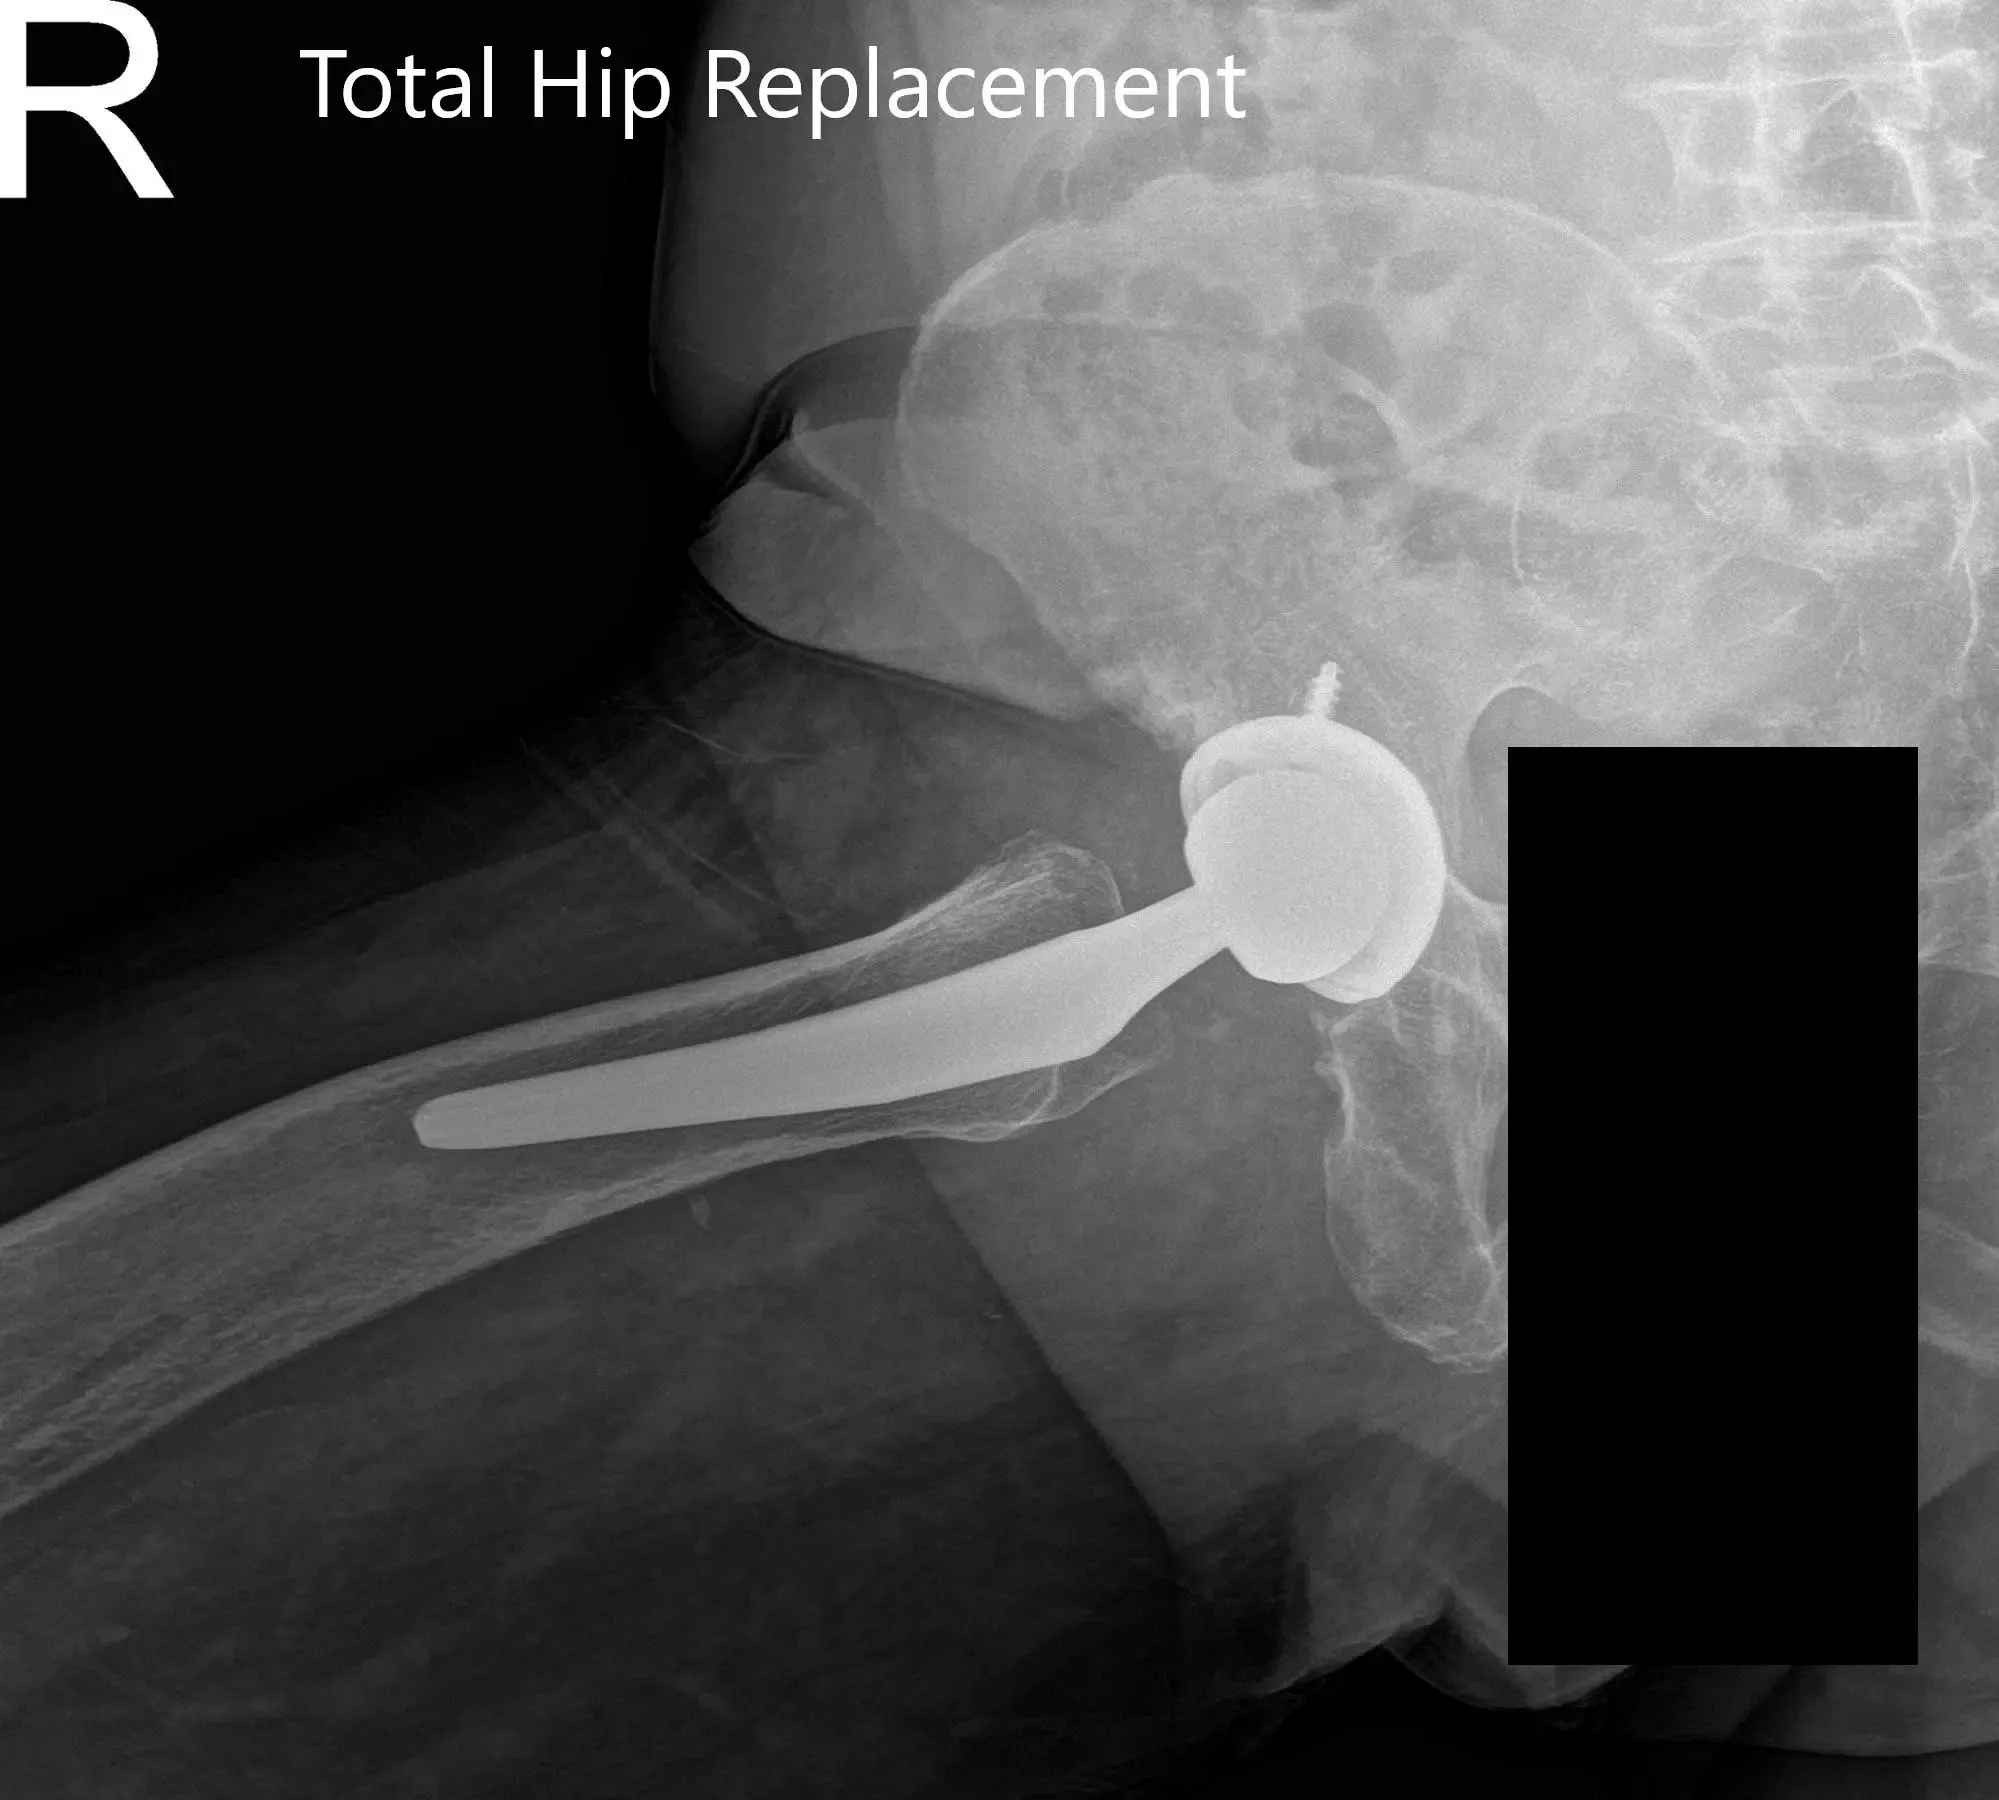

Postoperative X-ray showing the AP view of the pelvis and the frog-legged lateral view of the right hip

Postoperative X-ray showing the AP view of the pelvis and the frog-legged lateral view of the right hip (image-2)